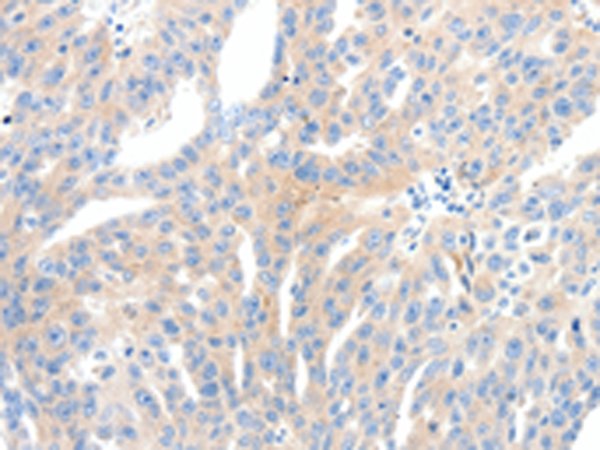

分类: 科研抗体货号: P11158别名: Fz-3应用: IHC反应种属: Human, Mouse